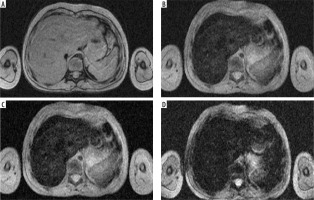

Figure 1

Iron overload in HEMOC sequence (TimeEcho: A – 2.38 ms; B – 9.53 ms; C – 16.67 ms; D – 23.82 ms), case of a 7-year-old patient after chemotherapy and radiotherapy, estimates the iron concentration in liver at 102 μmol/g dry weight (the R2* is estimated at 171.0 s–1 using a simple exponential decay) and spleen at 42 μmol/g dry weight (the R2* is estimated at 71.0 s–1 using a simple exponential decay)

A weak correlation between iron overload in other organs such as the heart, pancreas, and spleen with liver iron overload has been observed. A correlation with liver siderosis was only found in cases of heavy myocardial iron accumulation [7].